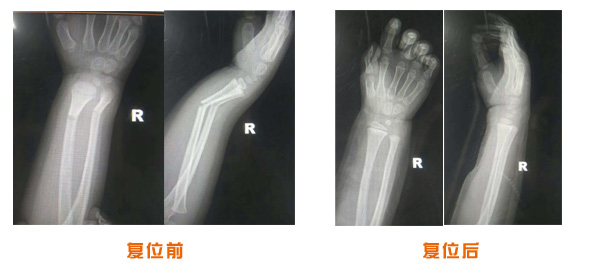

復(fù)位前后對比